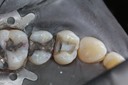

Kyle Chock #19 amalgam removal